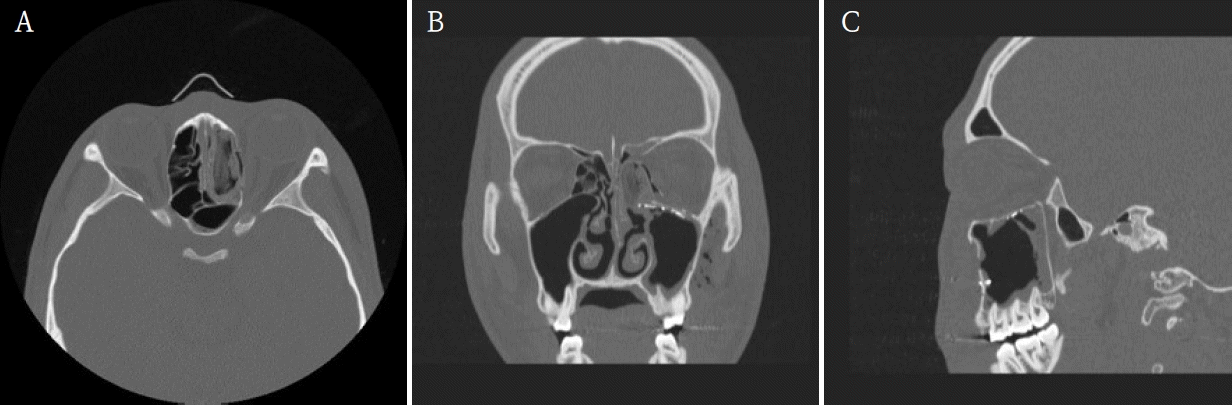

A 19-year-old male presented to the Emergency Department of Chonnam National University Hospital after sustaining facial trauma from slipping on the stairs. Severe swelling involving the left periorbital region and an approximately 2.0 cm laceration wound were observed on the left lower lip. The patient’s vital signs were stable, and neurological function was intact.Clinical examination revealed normal ocular motility, intact infraorbital sensation, and well-maintained globe position without diplopia or enophthalmos.A maxillofacial CT scan was performed for further evaluation. CT imaging demonstrated fractures of the left medial orbital wall, inferior orbital wall, and nasal bone (Fig. 1). The medial wall defect was located adjacent to the ethmoid sinus with partial herniation of orbital soft tissue. The inferior orbital wall fracture extended posteriorly with minimal displacement of the bony fragments, and a depressed nasal bone fracture was also confirmed.Initial management included primary closure of the lower-lip laceration under local anesthesia. Reduction of the orbital and nasal bone fractures was performed under general anesthesia using a multidisciplinary approach involving the Departments of Otorhinolaryngology and Oral and Maxillofacial Surgery.First, the medial orbital wall was repaired by the otorhinolaryngology team using an endoscopic transnasal approach with a navigation system (Fiagon Navigation System, Fiagon GmbH, Hennigsdorf, Germany). After uncinectomy and anterior ethmoidectomy, additional posterior ethmoidectomy was performed, followed by widening of the frontal and sphenoid ostia. This provided a clear surgical field for orbital compression and visualization of the left medial orbital wall fracture site (Fig. 2). The medial wall showed diffuse destruction with generalized herniation of the periorbita. After careful reduction of the herniated contents, a customized silastic sheet was inserted in an inverted U-shape (Fig. 3).Subsequently, the oral and maxillofacial surgery team performed intraoral access for reconstruction of the orbital floor. A vestibular incision approximately 3 cm in length was made, extending from the left canine to the first molar region. A bony window measuring approximately 15 × 10 mm was created in the anterior wall of the maxillary sinus to provide direct visualization of the inferior orbital wall defect. Herniated orbital tissue was carefully repositioned into the orbital cavity, and the orbital floor was anatomically reconstructed. A titanium miniplate with screws (DePuy Synthes, Oberdorf, Switzerland) was applied across the fracture line to achieve rigid fixation (Fig. 4). Layered closure was then performed to ensure proper wound healing and anatomical restoration.Finally, closed reduction of the nasal bone fracture was performed to restore nasal contour and symmetry. To maintain medial wall reduction and provide uniform compression, Merocel® (Medtronic Xomed, Jacksonville, FL, USA) was inserted into the ethmoid cavity. The operation proceeded smoothly without intraoperative bleeding, orbital content injury, or infraorbital nerve disturbance, indicating stable surgical control.Immediate postoperative CT confirmed successful reduction of both fractures. The patient experienced complete resolution of diplopia and ocular discomfort, while infraorbital sensation remained mildly decreased but improving. At two weeks, Merocel® packing was removed, and routine dressing was performed. At two months, follow-up CT and endoscopic examination demonstrated stable reconstruction, and the silastic sheet was removed (Figs. 5 and 6). The patient’s sensation had nearly recovered, and postoperative outcomes remained stable with preserved ocular movement, normal globe position, and proper occlusion.

Figure 1.

Preoperative maxillofacial computed tomographic images demonstrate the fractures of the left medial orbital wall, inferior orbital wall, and nasal bone. A. Axial view. B. Coronal view. C. Sagittal view.